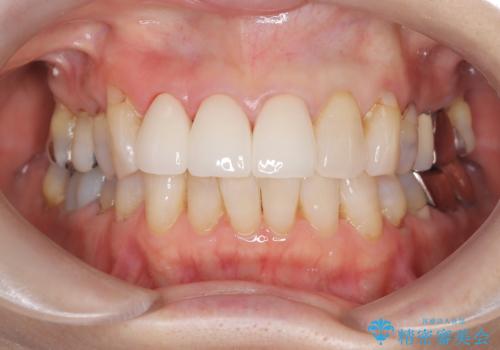

【外傷歯】根管治療から被せ物まで。

- 外傷により他院で治療中に転院を希望され受診されました。

前医では、抜歯も提案をされていましたが適切に治療を行うことで歯を保存することができました。

歯槽骨内水平性歯根破折は、抜歯の適応ではありません。